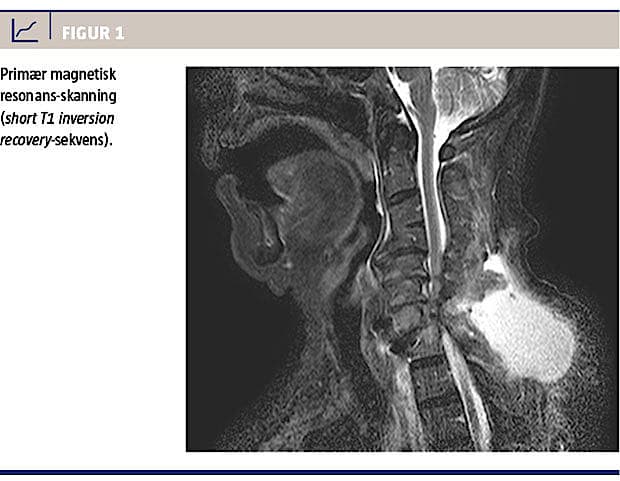

Anterior cervical interbody fusion (ACIF) indebærer, at man via anterior adgang udtømmer diskus til durasækken, hvorefter en cage (kunstig diskus/spacer), alternativt en graft, indsættes i diskusrummet. Man kan indsætte en skinne ventralt for den indsatte cage med henblik på stabilisering (Figur 1). ACIF er indiceret ved symptomgivende diskusherniering, spondylose eller ossifikation af lig. longitudinalis og ved fraktur med instabilitet [1].